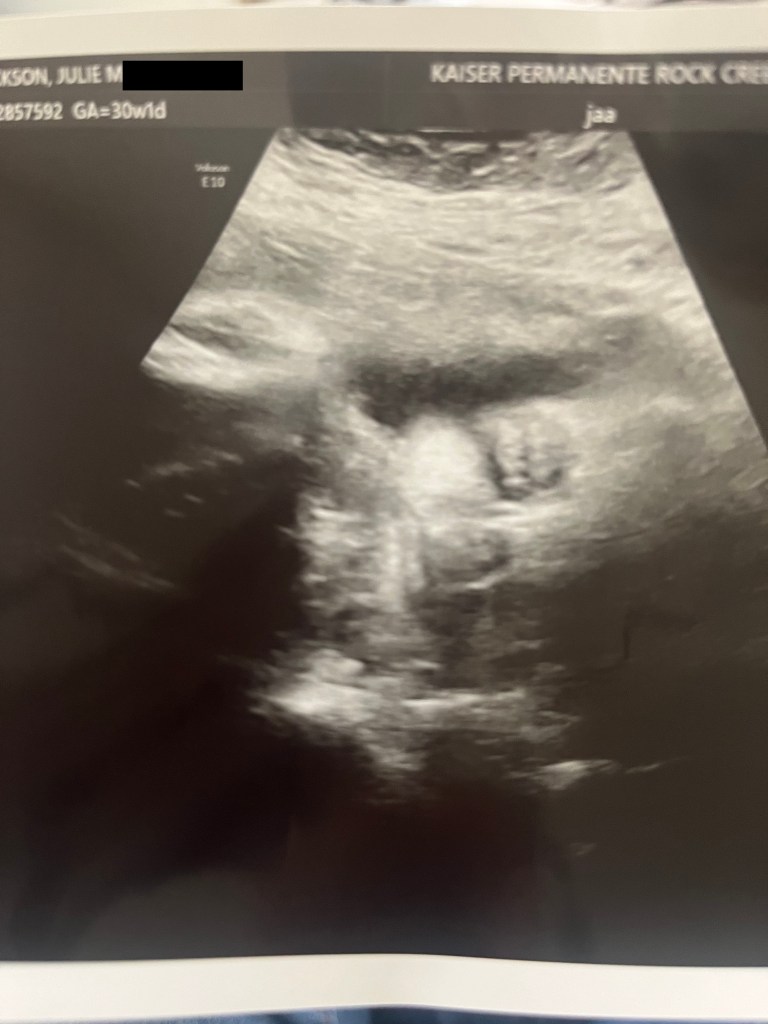

The morning of the scan arrived, and it was with the incredibly cool 3-D ultrasound used for the anatomy scan and the EKG. Once again, I got a nice, long look at little Mr. Rowan.

The ultrasound tech was telling me all about the measurements as she was taking them. His head circumference was right at 12 inches. It was 95th percentile.

It also reminded me that my eldest nephew had a big head when he was born at 41 weeks (14”). We’re nearly at that size, and I still had 10 weeks to go!

As far as his weight, Rowan was already at 4 lbs. (87th percentile)! My “What to Expect” app said he should be about three.

But a very cute Viking baby, according to this adorable ultrasound pic of his face!